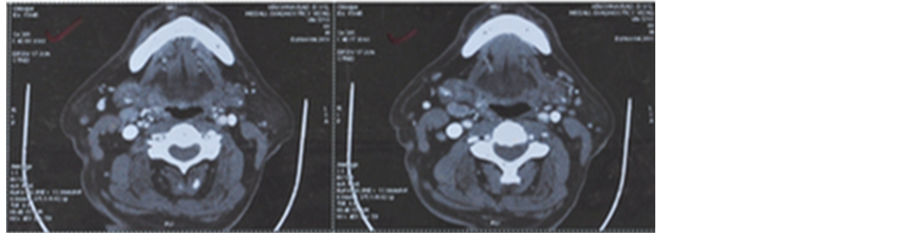

on oral examination. FNAC (fine needle aspiration cytology) from the neck node was reported as moderately differentiated squamous cell carcinoma. A panendoscopy was done to search for the primary. Even a CT scan failed to pick up the primary disease site. The patient was started on weekly cisplatin 40 mg/m2 and nimotuzumab 200 mg for 6 weekly cycles. Radiation was delivered to a total dose of 66 Gy/33 fractions/6½ weeks. CT scan done six weeks after the completion of RT showed regression of the nodal mass to 3 cm × 2 cm (partial response). PET CT was done to see the functional uptake and PET CT showed uptake (Figure 4). A radical neck dissection was performed for the residual node and the histopathological examination of lymph node did

Figure 4. (a) Pre-treatment CECT of neck showing large neck node measuring 7 cm × 6 cm with central necrosis; (b) Post treatment CT scan―Follow up CECT shows significant residual disease measuring 3 cm × 2 cm.

not reveal any residual disease. This shows the complete pathological response to treatment. Patient was followed up for 18 months.